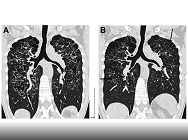

L'évaluation clinique et fonctionnelle respiratoire dans l'emphysème : pour quoi faire ?

- Date : 25/01/2019

- 0

0